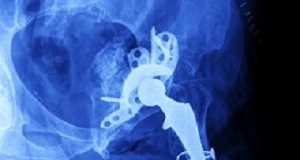

Tag: unicondylar knee replacement